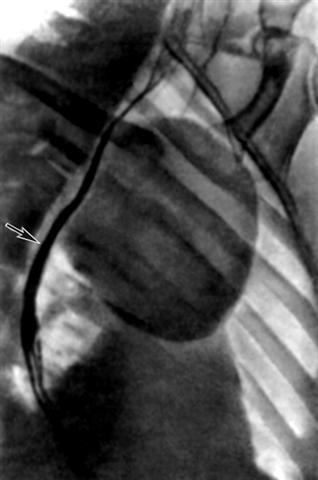

Рис. 2б). Рентгенограмма грудной клетки больной с дермоидом средостения: правая косая проекция, стрелкой указан смещенный дермоидом к позвоночнику контрастированный пищевод.